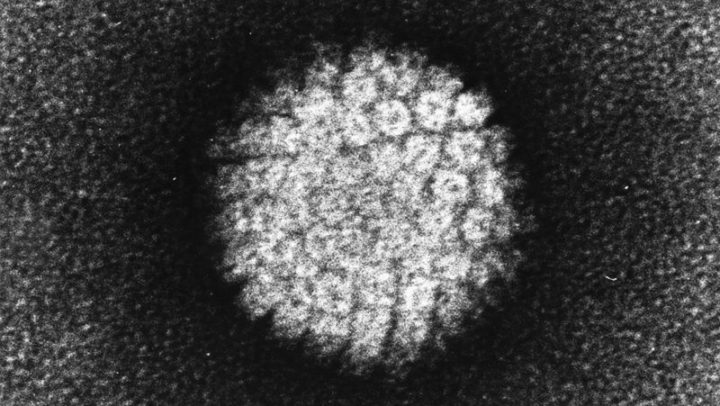

Neue Möglichkeit der Hautkrebsvorsorge – HPV-bedingte Plattenepithelkarzinome

Die Anzahl HPV-bedingter Plattenepithelkarzinome steigt, daher haben wir den Umfang unserer Hautkrebsvorsorge erweitert und bieten ab sofort einen Test an, der möglicherweise im Blut vorhandene Antigene gegen HPV-induziertes Tumorgewebe und Krebsvorstufen erkennt. Was sind HP-Viren (HPV) und wie steckt man sich mit HPV an? HPV bedeutet Humane Papillomviren. HP-Viren sind weit verbreitet, ca. 80 Pr...